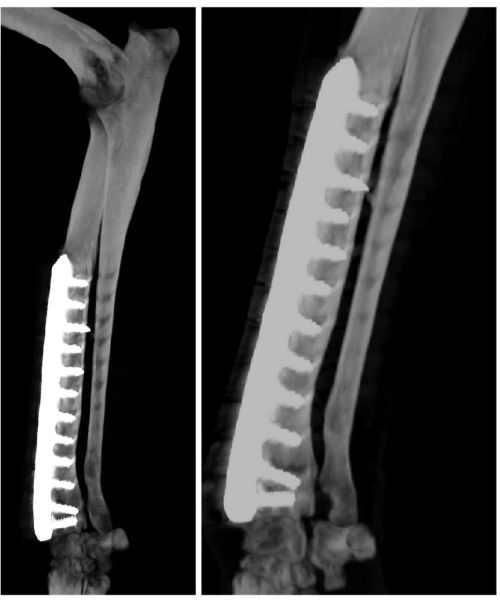

My 5-year-old Canaan dog (43 kg) had a distal radius-ulna fracture in his left front leg about three years ago, treated with a titanium plate and 12 locking screws. Since the surgery, he remained mildly lame but otherwise active and functioning well.

Recently, the lameness worsened - he began avoiding the leg completely. A CT scan indicated reasons to remove the implant, and a week and a half ago we went ahead with the removal surgery. He showed improvement over the next two days, but on day three, after suddenly jumping up in fear, he stopped using the leg again. An X-ray revealed a new fracture near the previous fixation site.

Attaching: CT before implant removal + Radiograph post-removal showing the new fracture.